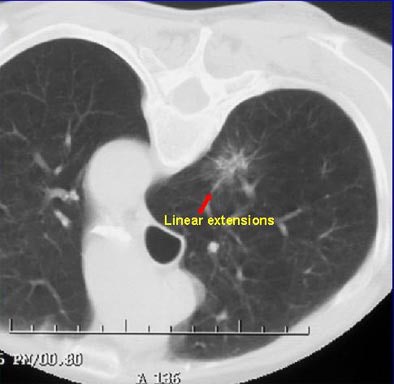

"These part-solid nodules can have linear extensions extending from them, in fact, very consistently. Pathologically they've been shown to correlate with extension of the lymphatic system," he said. "And you can also see this pattern (in) dilated bronchi within these part-solid lesions. It's interesting when you biopsy these, you often get fibrotic material that comes out; you have to be very careful. These tend to be in areas of fibrosis that perhaps causes the dilatation of these bronchi."

| Part-solid nodule with linear extensions. All images courtesy of Dr. David Yankelevitz. |